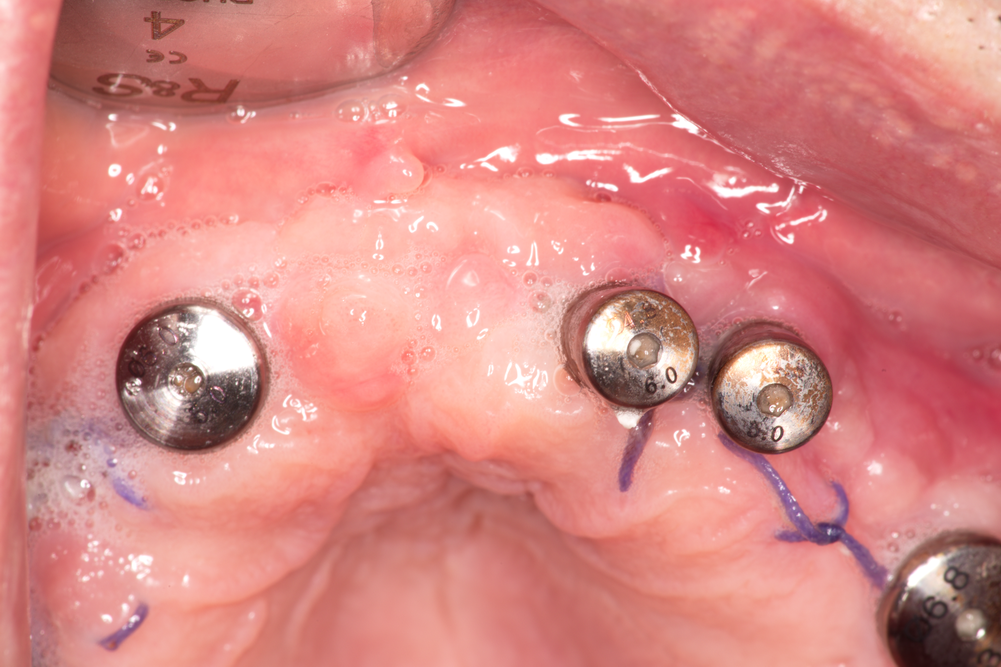

Добър заздравителен процес след поставянето на зъбни импланти. В значителен процент от случаите необходимите за тази цел оперативни интервенции са технически лесни, бързи и безпроблемни - като цяло процентът на постоперативните усложнения е доста нисък. Това се дължи на самата концепция на този лечебен метод - имплантира се стерилно чуждо тяло, което остава здраво фиксирано в областта на костните тъкани поради наличието на резба. Въвеждането на резбовите съединения в имплантологията представлява точно тази елементарна стъпка, която успя да предизвика революцията в световен мащаб. Всички останали рационализации и подобрения имат донякъде второстепенно значение - те са повече детайли. Разбира се, понякога дребните детайли са от голямо значение за получения краен резултат - това е валидно не само за медицината, но и за всяка една област на човешката дейност.

На горната снимка се виждат конци, които ще бъдат премахнати на същото посещение на пациента. Доста изследвания са посветени на вида на шевния материал, който е най-добре да се използва. Единственият извод е че за това няма универсално решение - всеки вид операционен конец си има своите предимства и недостатъци. Единствено кятгутът не се прилага в имплантологията, тъй като се резорбира сравнително бързо и освен всичко скоростта на неговата резорбция в устната кухина е дори по-голяма. Не е удачно да се оставя конецът да изпадне спонтанно, дори и да е резорбируем - максималният срок, за който шевът трябва да престои, е 10 - 12 дни. За този период той е фиксирал меките тъкани достатъчно стабилно и се превръща единствено в източник на инфекция. Резорбируемите шевни материали в повечето случаи натрупват по-големи количества зъбна плака и разпаднати материи; изключение от тази закономерност е коприната, която също се замърсява бързо.